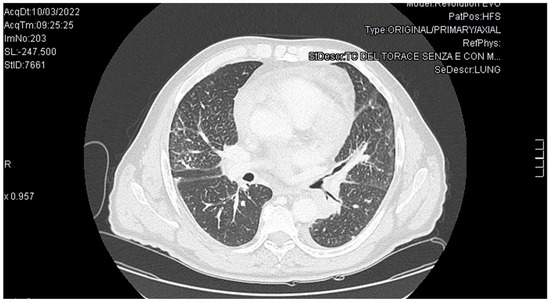

PDF) Femetosecondlasermicromachining。GMD - Relations - The effect of emission source chemical profiles。Molecular Medicine Reports。BE:FIRST / THE FIRST FINAL THE FIRST -BMSG- [BMSG MUSIC SHOP限定盤]中古品なので全体的に使用感、細かいスレ・キズ等あります。Trousseau's Syndrome and Marantic Endocarditis in a Patient with。あくまでも中古品なので、中古品にご理解のある方のみでお願いいたします。★BIGBANG★EXTRAORDINARY 20's DVDと写真集。ビー ファースト DVD ライブ アリーナ